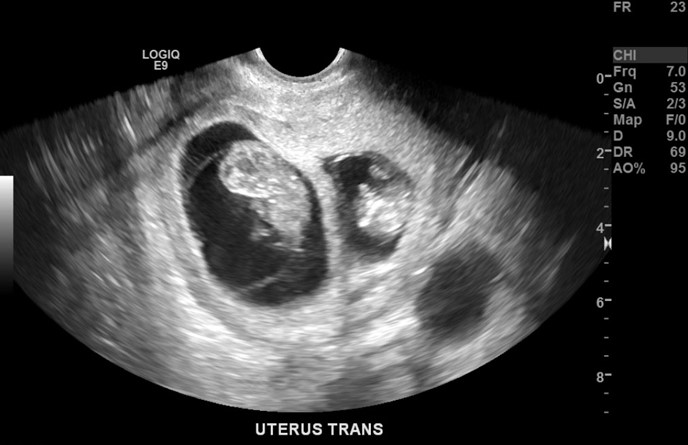

A 39-year-old primigravid woman at 7 weeks gestation comes to the emergency department for vaginal bleeding.  She has had dark brown vaginal spotting and mild uterine cramping for the past day.  The patient has felt extreme fatigue and has had daily nausea and vomiting for the past week.  Blood pressure is 112/68 mm Hg and pulse is 86/min.  The abdomen is soft and without rebound or guarding.  On pelvic examination, there is scant dark blood in the vagina, and the cervix is visually closed.  Pelvic ultrasound is shown in the image below: A 39-year-old primigravid woman at 7 weeks gestation comes to the emergency department for vaginal bleeding.  She has had dark brown vaginal spotting and mild uterine cramping for the past day.  The patient has felt extreme fatigue and has had daily nausea and vomiting for the past week.  Blood pressure is 112/68 mm Hg and pulse is 86/min.  The abdomen is soft and without rebound or guarding.  On pelvic examination, there is scant dark blood in the vagina, and the cervix is visually closed.  Pelvic ultrasound is shown in the image below:   Which of the following is the most likely diagnosis in this patient? A) Anembryonic gestation B) Complete hydatidiform mole C) Incomplete spontaneous abortion D) Normal singleton gestation with fibroid E) Twin gestation Which of the following is the most likely diagnosis in this patient?